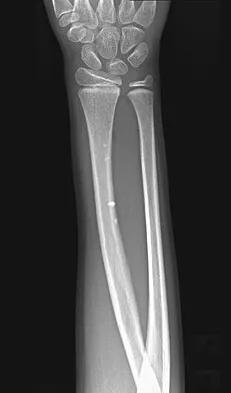

Which of the following choices best describes the fracture pattern shown in Figures 2a through 2c?

Explanation

The fracture pattern shown in the radiographs is a fracture of the posterior column. The only line interrupted on the AP pelvis is the ilioischial line. The obturator oblique view shows that the iliopectineal line is intact as is the outline of the posterior wall. The iliac oblique view shows an interruption of the ilioischial line and an intact anterior wall. Therefore, this fracture is a fracture of the posterior column. Letournel E, Judet R: Fractures of the Acetabulum, ed 2. Berlin, Germany, Springer Verlag, 1993.